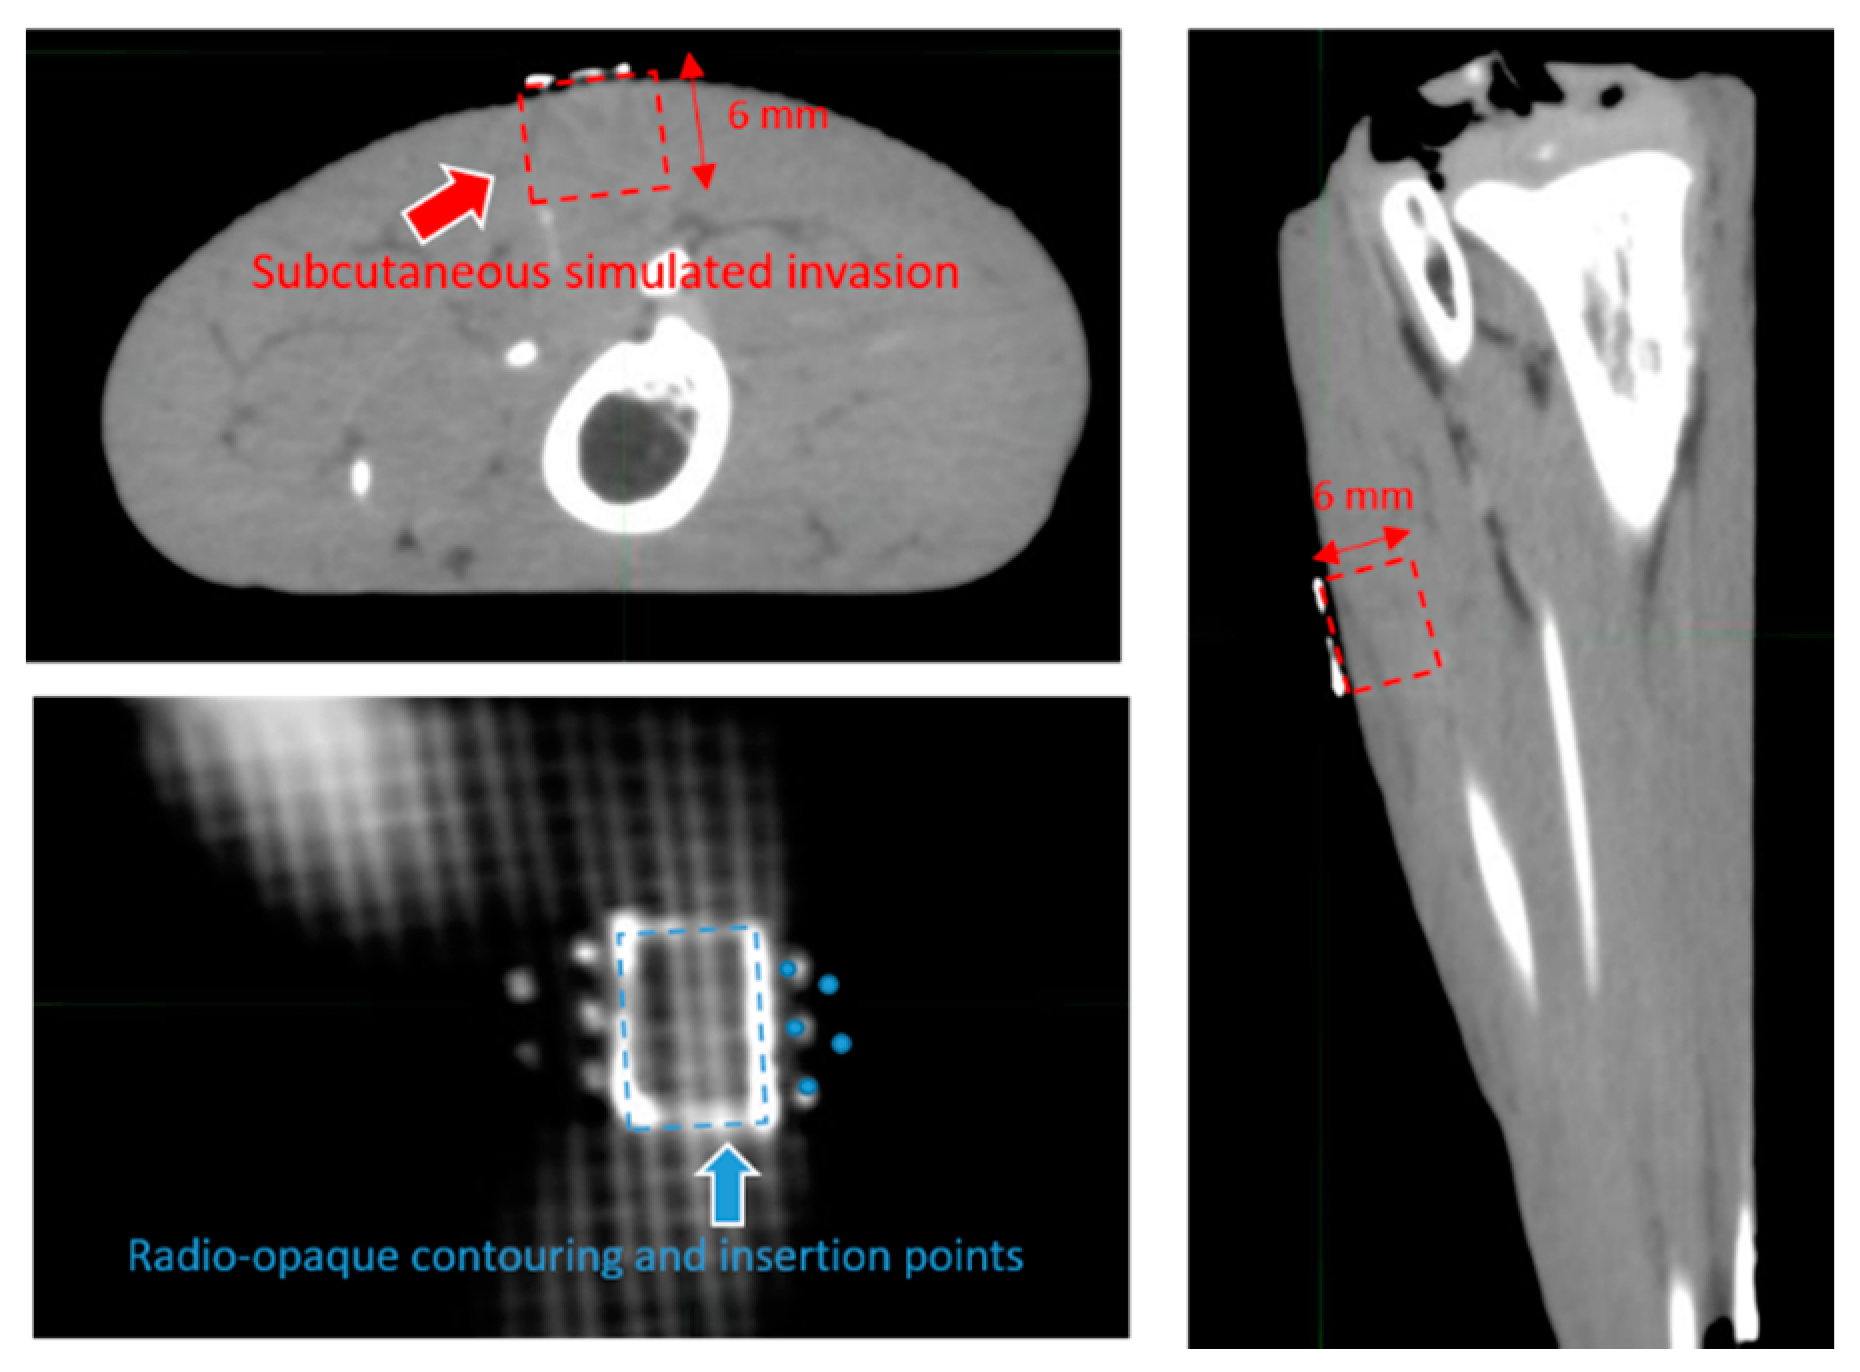

2.2. Template Based Planning Phase 1: Phantom Training

2.3. Template Based Planning Phase 2: Patient Application

3.1. Template Based Planning Phase 1: Phantom Training

3.2. Template Based Planning Phase 2: Patient Application